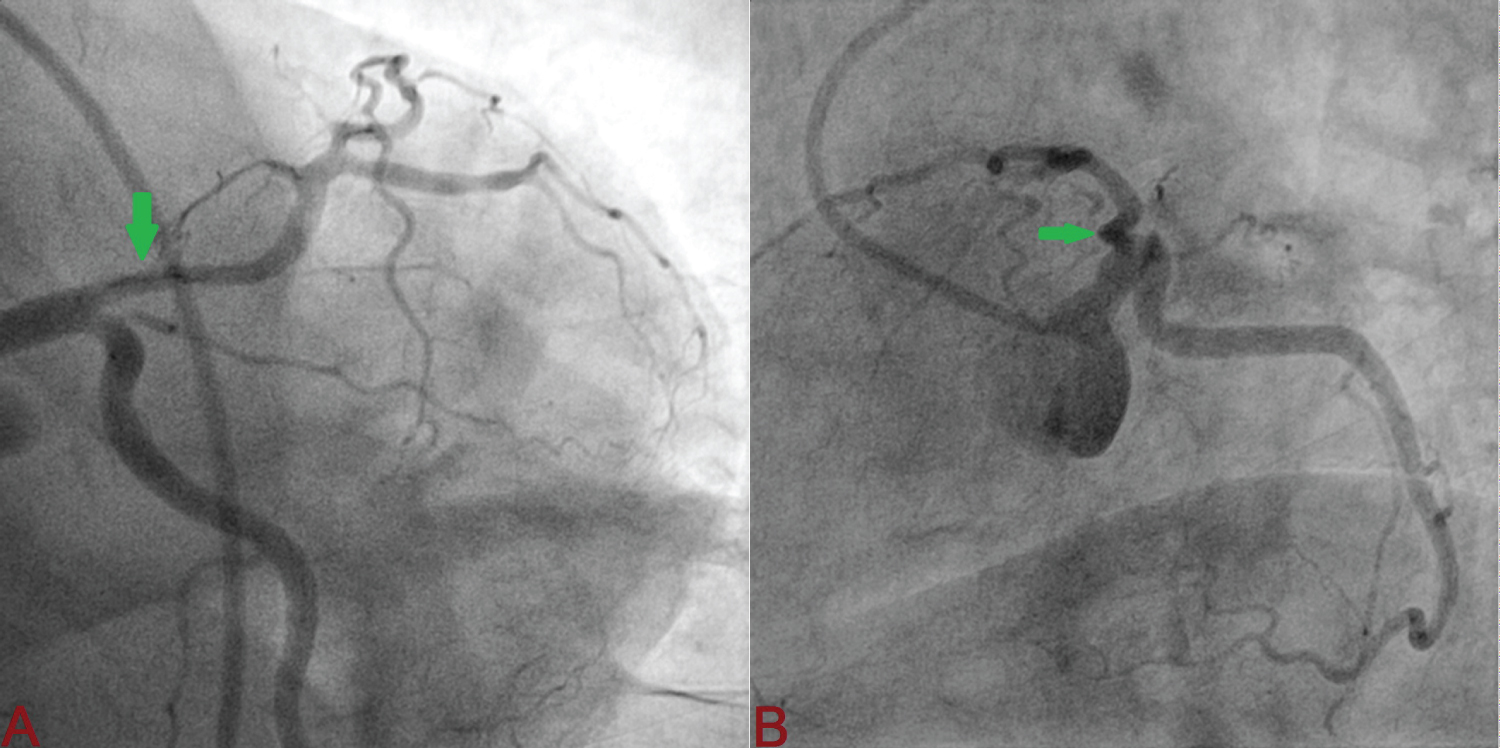

A 32-year-old apparently healthy male presented with excruciating chest pain with diaphoresis of 2-hour duration. His pulse rate was 85 beats/min and blood pressure was 110/84 mmHg. Other physical findings were all normal. Electrocardiogram showed normal sinus rhythm and ST-elevation in V1-V6 with reciprocal changes in inferior leads. An echocardiogram revealed regional wall motion abnormality in left anterior descending artery territory (LAD) with mild left ventricular (LV) systolic dysfunction (ejection fraction = 45%). His routine blood examinations were normal. He was loaded with aspirin 300 mg, clopidogrel 300 mg and thrombolysed with 40 mg Tenecteplase. At 90 minute, chest pain was persistent with little resolution of ST segment (≤ 50% from initial elevation) which indicated failed lyses. Coronary angiography was performed through transfemoral after obtaining written consent. LAD showed large, spontaneous spiral dissection with flap beginning from osteo-proximal segment extending up to mid segment involving first diagonal branch which was labelled as Type-D SCAD (Figure 1 and Figure 2). As the origin of dissection flap was appreciated on first injection and originating away from the ostial segment of LAD, it ruled out iatrogenic dissection. The rest of his coronary trees were normal. PCI was advised PCI but patient refused. He was conservatively managed with Ecospirin 75 mg, Clopidogrel 75 mg, Rosuvastatin 10 mg, Ramipril 5 mg and Metoprolol 100 mg. Repeat angiogram 4-weeks later revealed complete healing of dissection along with borderline lesion (Figure 3). Echocardiography indicated normalization of systolic function (ejection fraction-70%). As his treadmill test was negative for exercise induced myocardial ischaemia, he was managed conservatively.

Figure 2: Spiral dissection beginning from osteo-proximal left anterior descending artery involving large diagonal branch (A: Left anterior oblique shallow view; B: Spider view. Yellow arrow indicate intimal flap). View Figure 2